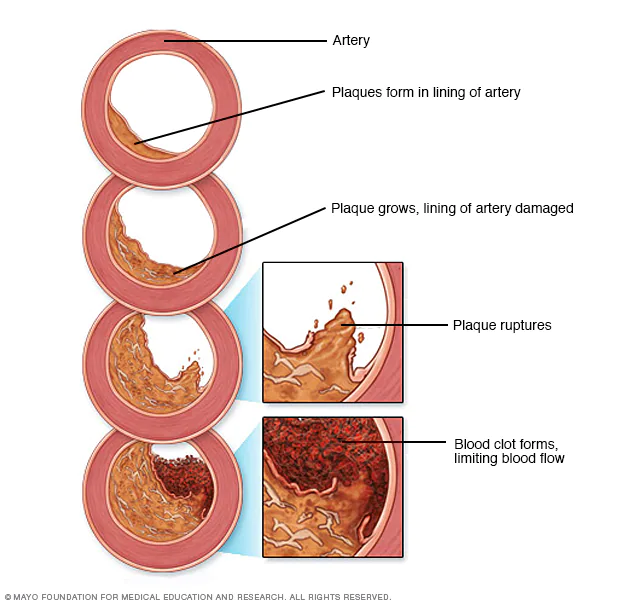

Η περιφερική αγγειοπάθεια είναι μια διαταραχή της κυκλοφορίας που προκαλεί την στένωση ή την απόφραξη των αγγείων. Το υλικό που φράσσει τις αρτηρίες αποτελείται κυρίως από λίπος και είναι γνωστό ως αθηρωματική πλάκα και η κατάσταση ως αθηροσκλήρωση.Η Περιφερική Αρτηριακή Νόσος (ΠΑΝ)

Οτιδήποτε διακόψει τη φυσιολογική αυτή λειτουργία όπως για παράδειγμα η στένωση των αρτηριών (αθηροσκλήρωση), έχει σαν αποτέλεσμα τη δημιουργία ανάλογων συμπτωμάτων από τους ιστούς και τα όργανα που αρδεύονται από την αρτηρία που παρουσίασε τη βλάβη. Αυτό προϋποθέτει στένωση της αρτηρίας μεγαλύτερη από 70%.

Ανάλογα με το βαθμό της στένωσης της αρτηρίας η κατάσταση μπορεί να γίνει πολύ επικίνδυνη αν αφεθεί χωρίς θεραπεία. Συγκεκριμένα, όταν η στένωση της αρτηρίας ξεπεράσει το όριο του 70%, μειώνεται σημαντικά η παροχή του αίματος στο αντίστοιχο όργανο που τροφοδοτεί η αρτηρία, και μπορεί να δημιουργήσει τα ανάλογα συμπτώματα. Στο τελικό στάδιο, παρατηρείται ολική απόφραξη αρτηρίας με πολύ σοβαρές συνέπειες στο όργανο του σώματος που τροφοδοτούνταν από το πάσχον αγγείο.

Η αρτηριακή εμβολή όπου θρόμβος πηγμένου αίματος, συνήθως από τη καρδιά, μεταφέρεται με την κυκλοφορία στα κάτω άκρα και αποφράσσει κάποια αρτηρία. Εμβολή μπορεί να έχουμε και από υλικό ανευρύσματος κοιλιακής αορτής ή λαγονίου ή ιγνυακής αρτηρίας (αθηρο-εμβολισμός)Οξεία θρόμβωση. Σε ήδη ανεπτυγμένη αθηρωματική πλάκα μιας αρτηρίας των κάτω άκρων αναπτύσσεται πάνω της θρόμβος, ο οποίος την αποφράσσει 100%